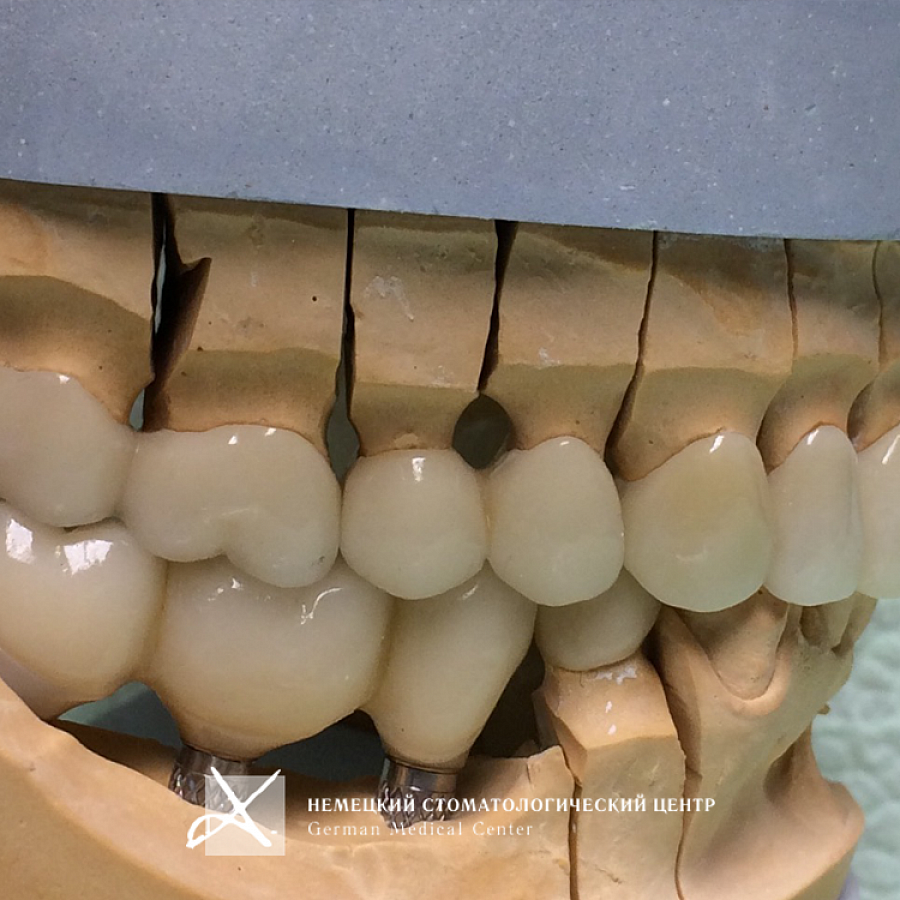

Протезирование несъемными конструкциями на имплантатах прекрасно восстанавливает целостность зубных рядов, возвращает возможность полноценного жевания, возможность улыбаться и жить полноценной жизнью. Правильно проведенное лечение позволяет создать эффект натурального зуба и естественный вид десны в области имплантатов.

Пациентке проведено полноценное восстановление зубных рядов конструкциями с опорой на зубы и имплантаты. Коронки и абатменты изготовлены из диоксида циркония. Во время подготовительных мероприятий пациентка пользовалась временными конструкциями.